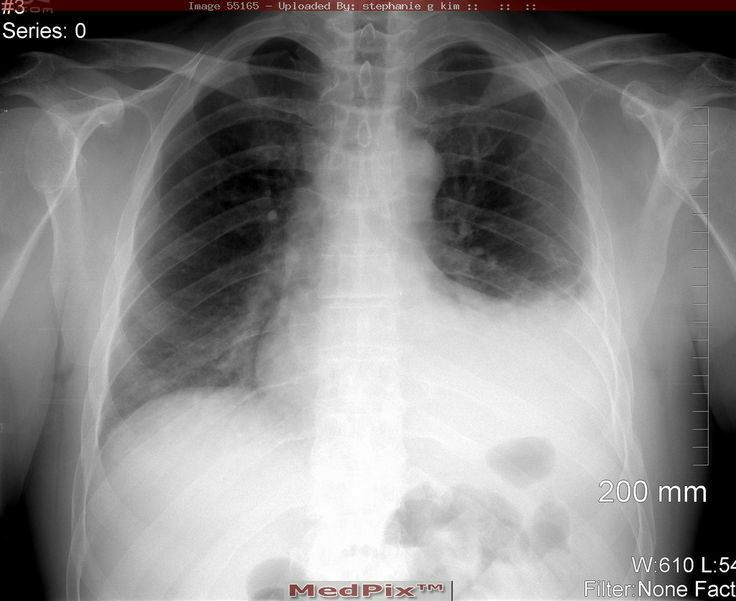

Hemothorax❤

Collection of the blood in the pleural cavity